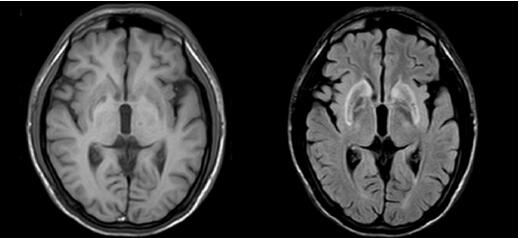

正常人头颅磁共振MR:

患者头颅磁共振MR:

T1加权像壳核、丘脑等处低信号病灶,苍白球呈等信号;T2加权像壳核、丘脑高或稍高信号病灶,但苍白球出现特征性低信号(可能与铜沉积的顺磁作用有关)。